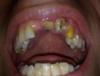

Здравствуйте у меня проблема с зубами. Т.е. коронки выпали долгое время держались. Сейчас трудности с деньгами ходил к стоматологам мне говорят нужно делать новые. По деньгам получается от 25000р. Туда входит удаление второго зуба (верхний) он без нерва, и новые коронки 4 зуба. Я разместил фото ниже если кто может сделать недорого ну например те которые выпали закрепить снова пусть это будет временно хотя бы на 2-3 месяца, был был благодарен. Не знаю может штифт установить на первый зуб. Или еще какой нибудь вариант. Главное не дорого сейчас трудно с деньгами. В ближайшее время займусь серьезнее т.е. новые коронки.

post-22734-0-43981900-1319291140_thumb.jpg

post-22734-0-58135000-1319291143_thumb.jpg

post-22734-0-17454000-1319291147_thumb.jpg